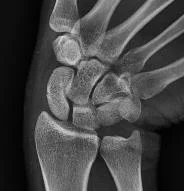

- Plain x-ray: (law of two’s)

Law of Two’s

- Plain x-ray: (law of two s)

- Two views: AP and Lateral

- Two joints: joint above and joint below

- To show other injuries

- To assess rotation

- Two limbs: for comparison

- more in children to compare epiphysis

- Two occasions

- e.g. stress fractures

- e.g. scaphoid fracture

- Two injuries

- e.g. patellar fracture and hip injury

- e.g. calcaneal fractures & spine injuries

- …and two Doctors!!

- Special views:

- Ankle mortis

- Calcaneal view

- Scaphoid views

- Shoulder dislocation: axial view

- Acetabular fractures: 45° tilt views

- Stress views

- Traction views

- Functional flexion/extension (spine)